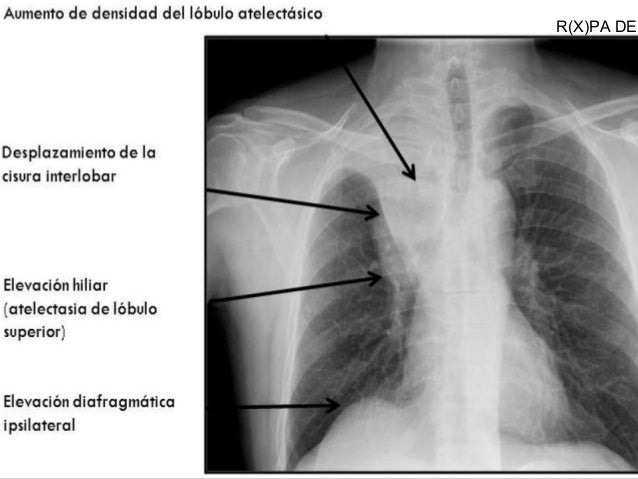

Sindromes Parenquimatosos Pulmonares